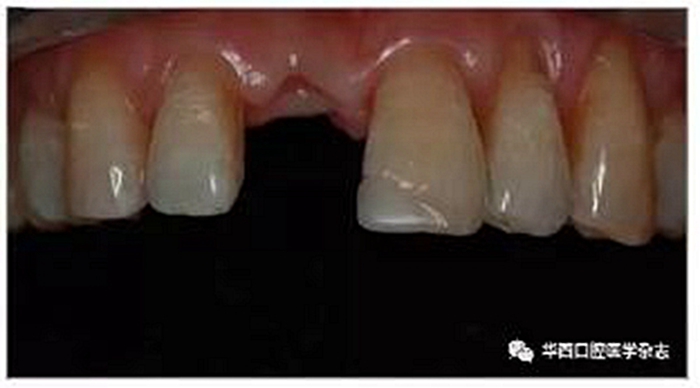

術(shù)前對患者的狀況進行綜合評估,與患者進行溝通確定治療方案。以1例右側(cè)上頜中切牙(11牙)缺失患者為例說明治療步驟。該患者右側(cè)上頜中切牙缺失3個月,左側(cè)上頜中切牙(21牙)近中切角原樹脂充填體不美觀(圖1)。

圖1 修復前影像